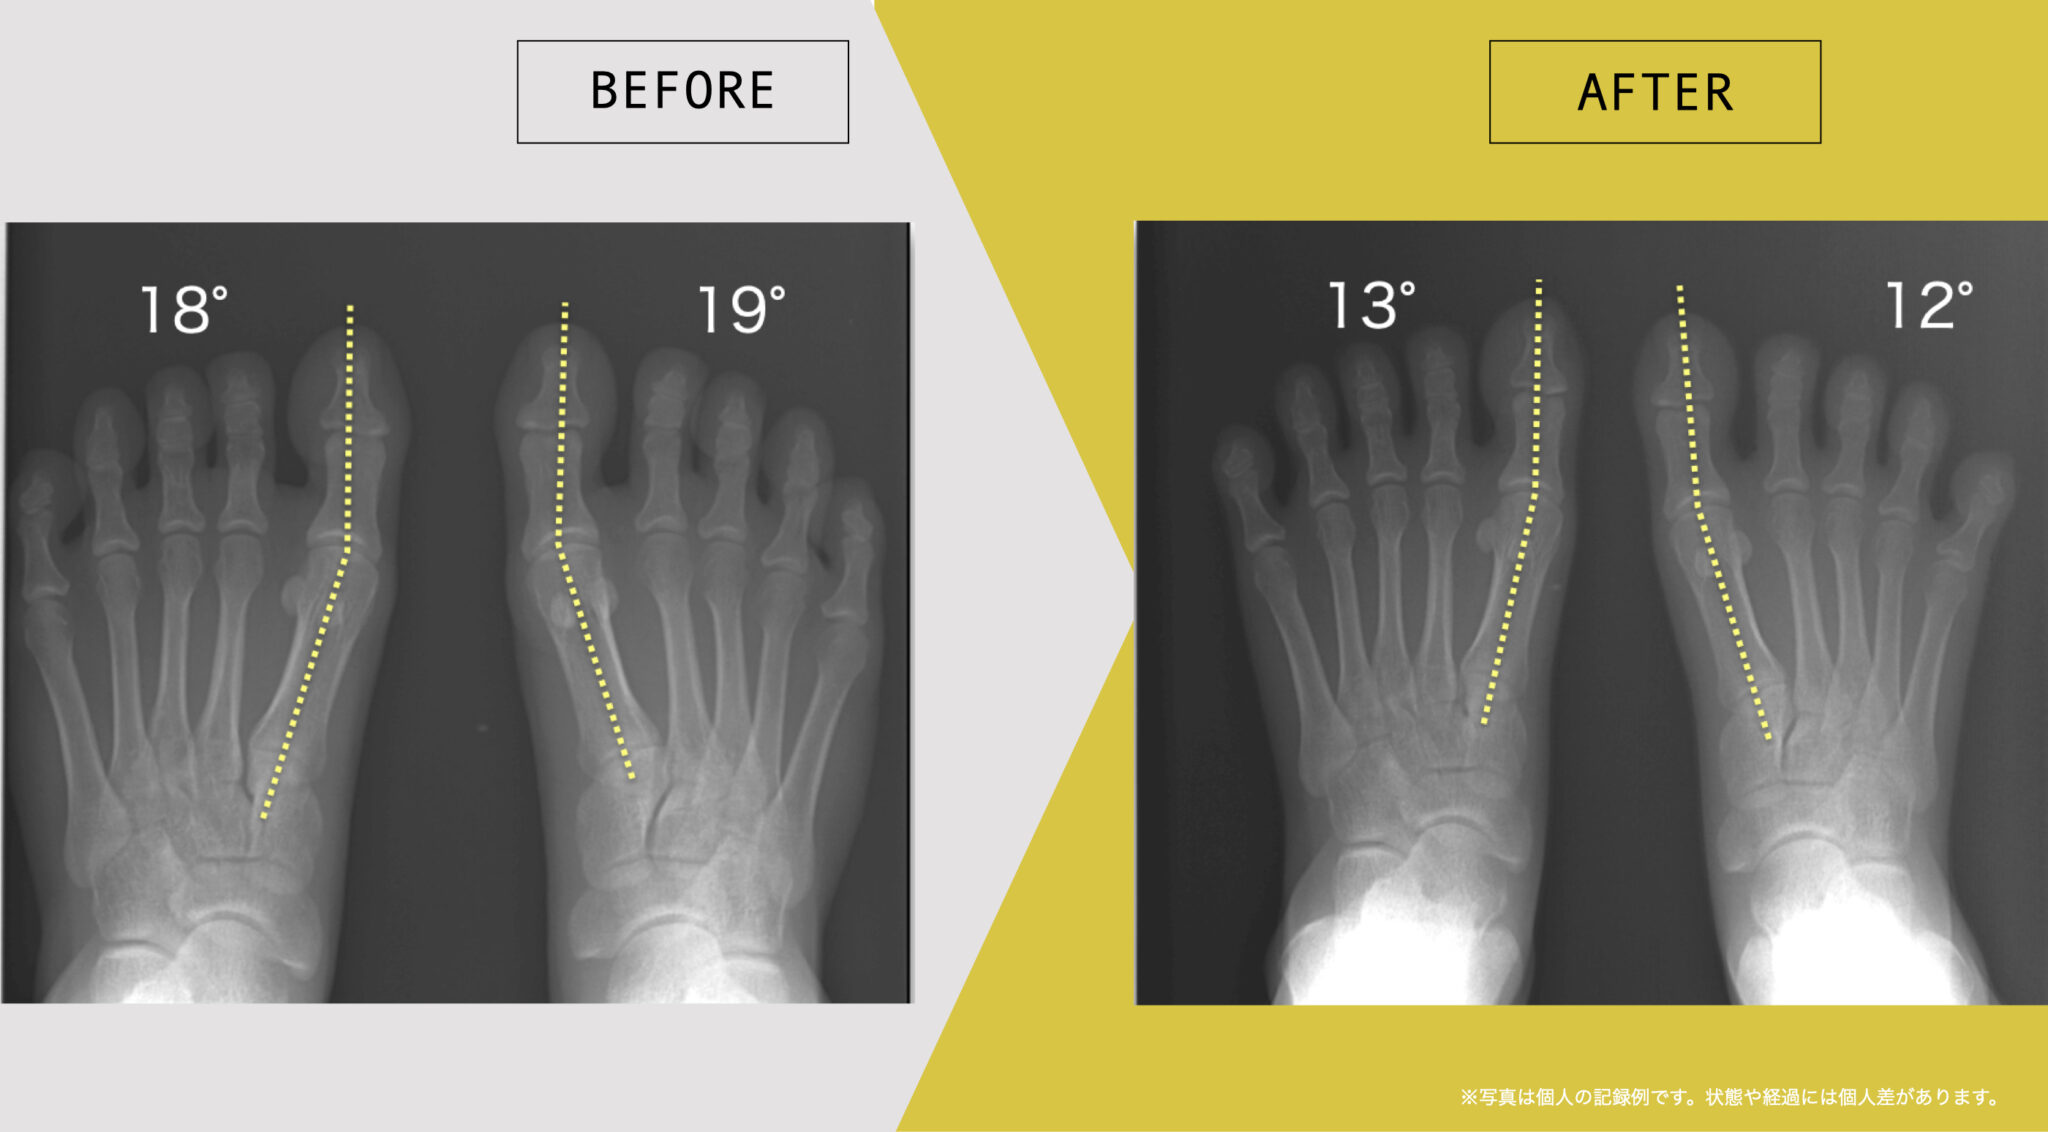

足指や姿勢の状態に関する記録例

ここでは、日常生活の中で足指のセルフケアを継続された方について、足指や姿勢の状態を記録した一例をご紹介します。

これらは、医療的な効果や症状の改善を示すものではなく、生活習慣の中での足指の状態を個別に記録した参考例です。同様の結果が得られることを示すものではなく、状態や経過には個人差があります。